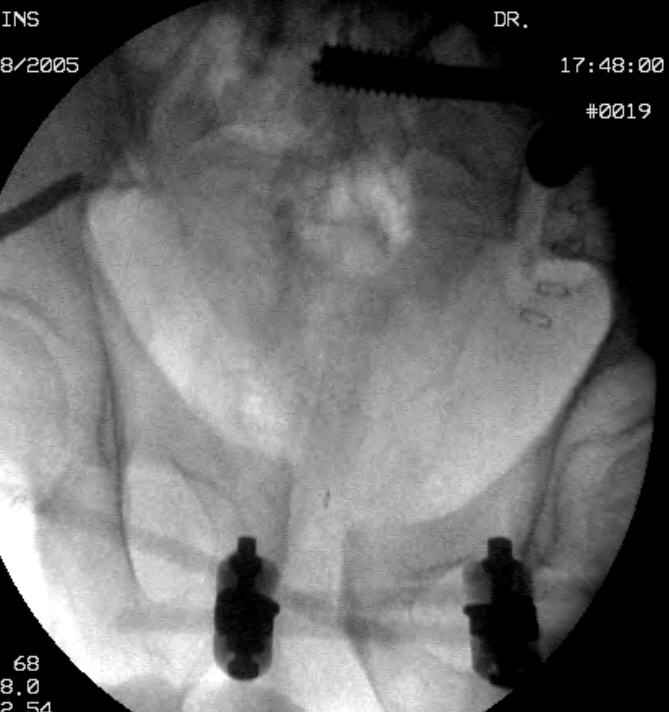

Hello gentlemen- Case is 52 YO male, fell out of treestand while deerhunting. He is 6 ft, approx. 260-275 lbs. Was hemodynamic unstable at local ER, sent to our Trauma center where circumferential pelvic binder placed and pt. stabilized with fluid, blood, and rewarming. Angiography not performed. An extraperitoneal bladder disruption was found, uro elected to treat non-operatively. Initial xray (not shown) demonstrated 5-7 cm wide at symphysis and SI joint. The first image attached is of CT once binder is in place. On post trauma day 5 the pt was taken to OR for ORIF of his iliac wing fracture and SI dislocation. The swelling/3rd spacing of fluid in the area of symphysis was profound, but quite acceptable posteriorly. Patient was prone for procedure, as I thought too difficult to fix the wing in lateral position. Of course the repair of wing was easy, but reduction of SI very demanding. The Floro images document the residual lack of reduction. That was the closest I could get it using 6mm joystick in wing, and clamp on sacrum and clamp through notch. The fixation was (initially) rigid. Anterior ex fix with supra-acetabular pins was placed due to condition of soft tissues, massive "beer-belly" overhanging the crest. Post trauma day ten patient's xray shows failure of posterior construct. Plan was to perform revision orif once soft tissues resolve considerably for full anrterior fixation and posterior fixation. However, while Im away for holiday (on Post trauma day 15), pt is developing septic clinical appearance, and trauma suspects pelvic abcess near symphysis and performs I and D - finds nothing but no primary closure performed. Posterior tissues/incision continue to look healthy. Now is post trauma day 17, pt is still tubed/on dopamine/and wbc still elevated, anterior incision still packed open. Clearly must get to bottom of possible sepsis, but then what? Thanks for you time - sorry for such lengthy clinical description. Thomas Schaller Kalamazoo, Michigan

5. Your caudal iliosacral screw is/was in his spinal canal... it's low and posterior and the lateral fluoro image confirms this... a postop CT will show it (or it's trail at this point)... canal screws do not hold.

6. Frames (even fancy new-style low ones) have poor mechanical stability when compared to symphyseal internal fixation...unstable rings in fat (and skinny) folks demand stable anterior and posterior stabilities... a frame

can't get you there... consider it a helper/support at best.